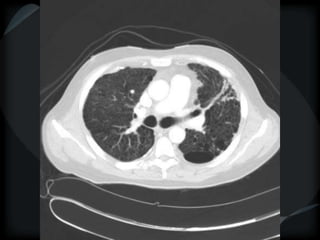

Emphysema - CL

Emphysema - PA

CL + PS emphysema